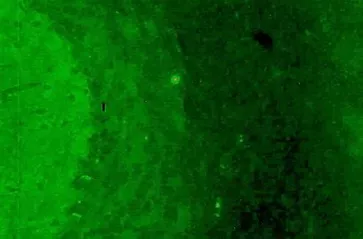

• Рецепторный тип свечения

Рецепторный тип свечения

Характеризуется специфическим свечением молекулярного слоя мозжечка и встречается у пациентов с NMDA, AMPA, GABAb, LG1, CASPR2 и DPPX антител.

• Рецепторный тип свечения нейронов встречается при следующих неврологических расстройствах: анти-NMDA энцефалит, лимбический энцефалит, нейромиотония, синдром Морвана, энцефаломиелит. Эти антитела ассоциированы с такими заболеваниями, как мелкоклеточная карцинома легких, злокачественная тимома, карцинома легких, карцинома молочной железы, овариальная тератома, тестикулярная тератома, карцинома щитовидной железы, карцинома почек, карцинома матки. Наиболее часто данный тип свечения встречается при наличии NMDA, LG1, CASPR2 антител.